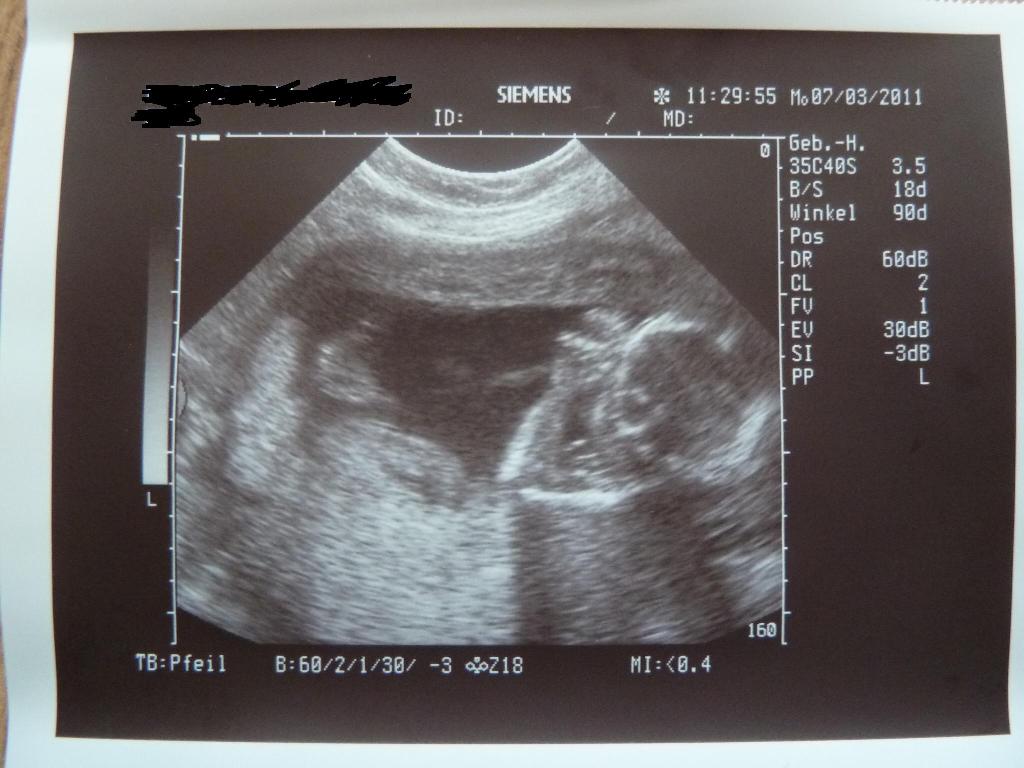

@all: war heute in der Kiwu zum Ultraschall. Ursprünglich wollte ich den Termin absagen, aber nach dem Gruseltermin letzten Montag habe ich mir das ganz schnell anders überlegt…So konnte ich heute endlich mal wieder ausführlich mein Babylein ansehen und danach ging es mir auch gleich vieeeeel besser. Habe heute auch endlich mal wieder ein paar Bildchen bekommen. Die stelle ich euch gleich mit ein. Der Kinderwagen wurde heute geliefert und so habe ich gleich mal fleissig alles geknipst. Bilder folgen. Seid alle lieb gegrüßt!!!